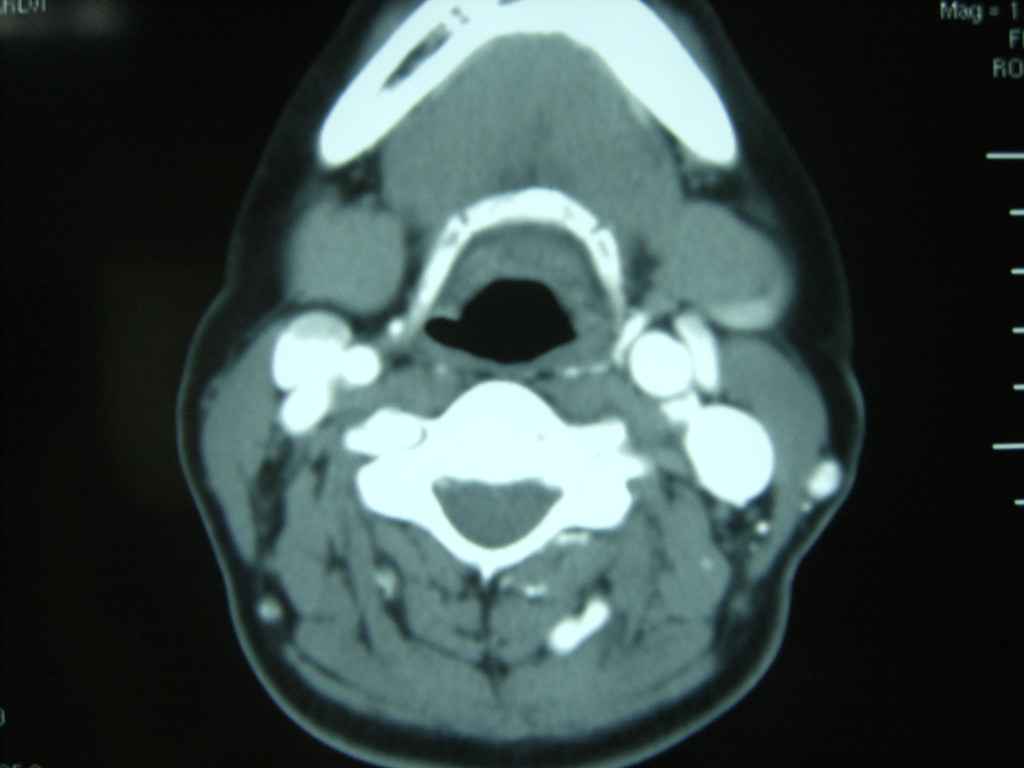

女,48岁,左颈部增粗,不适一年,伴左侧面麻.

增强明显,考虑左侧颈动脉体瘤可能性大。

颈动脉体瘤,不除外副节瘤。

左侧颈动脉体部肿瘤(以化学感受器肿瘤)可能性大。

答案:颈动脉体瘤  此患者已于赤峰220医院手术,